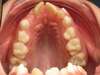

Avant traitement

Avant disjonction